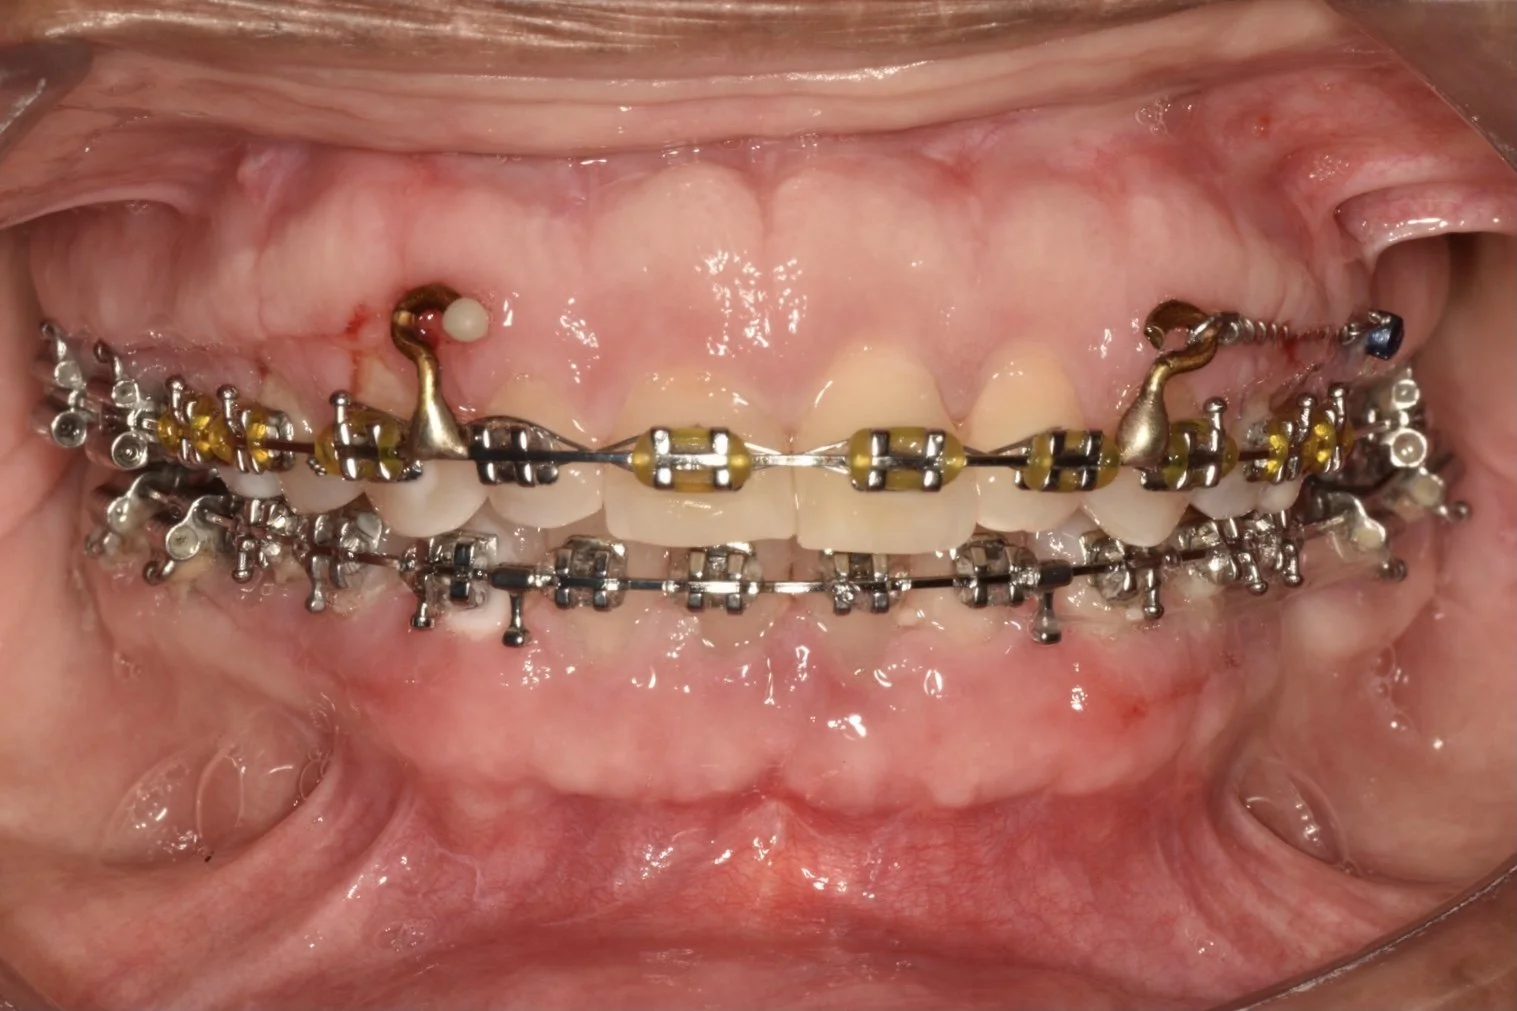

THE CROSSBITE CORRECTION

THE CROSSBITE CORRECTION